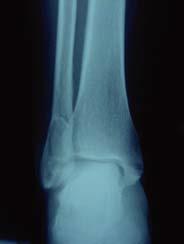

Patient consulte aux urgences après une chute, à l’examen clinique pas de luxation , oedème de la cheville important, pas de souffrance cutanée. Diagnostic? Quel a été le mécanisme lésionnel probable?

Fracture bimalléolaire de cheville intertuberculaire

mécanisme en rotation externe forcée